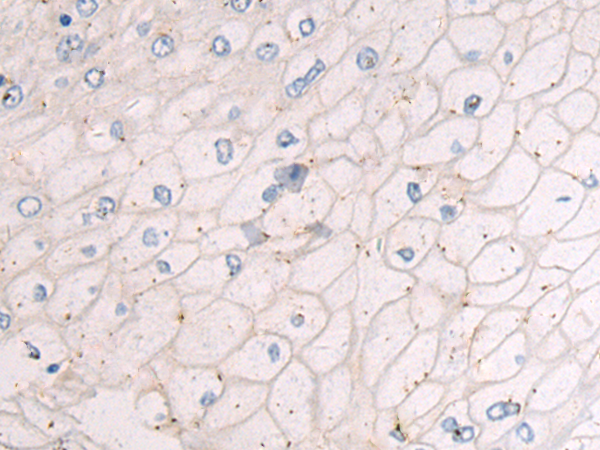

分类: 科研抗体货号: P10614别名: RIF; ARHF应用: WB,IHC反应种属: Human, Mouse